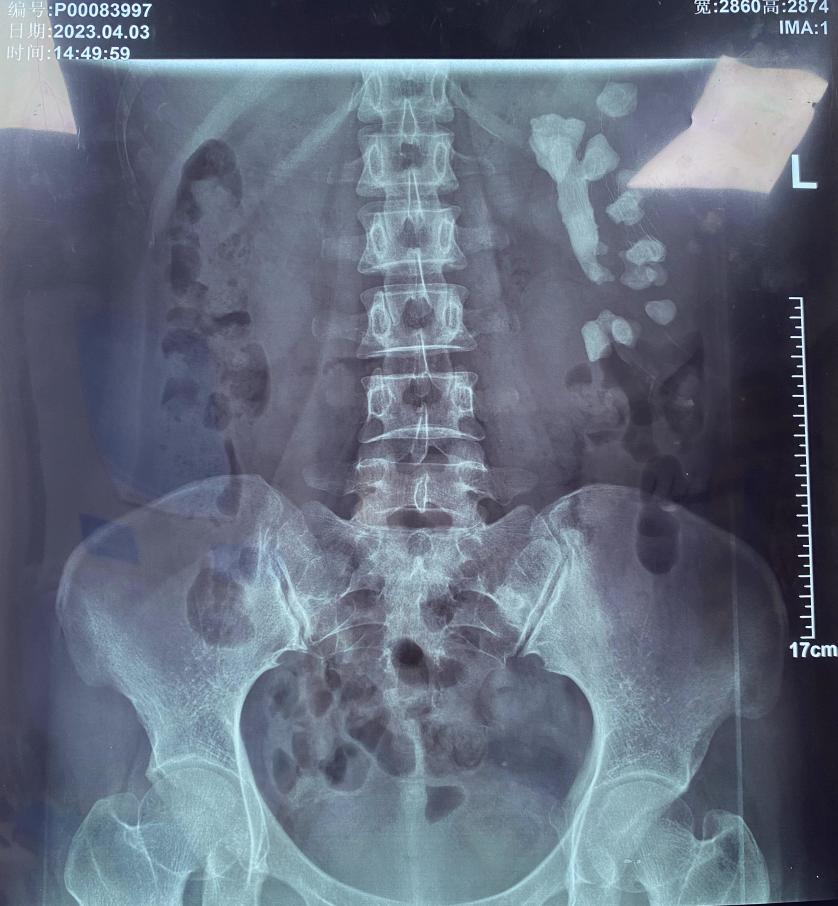

從不體檢,腎臟先天畸形不自知 超大號(hào)“珊瑚”結(jié)石險(xiǎn)撐壞女子左腎通訊員 金京“我也不知道結(jié)石是什么時(shí)候長(zhǎng)的,從來(lái)都不痛?!弊罱?,來(lái)自湖南的宋女士是一肚子苦水,左腎···